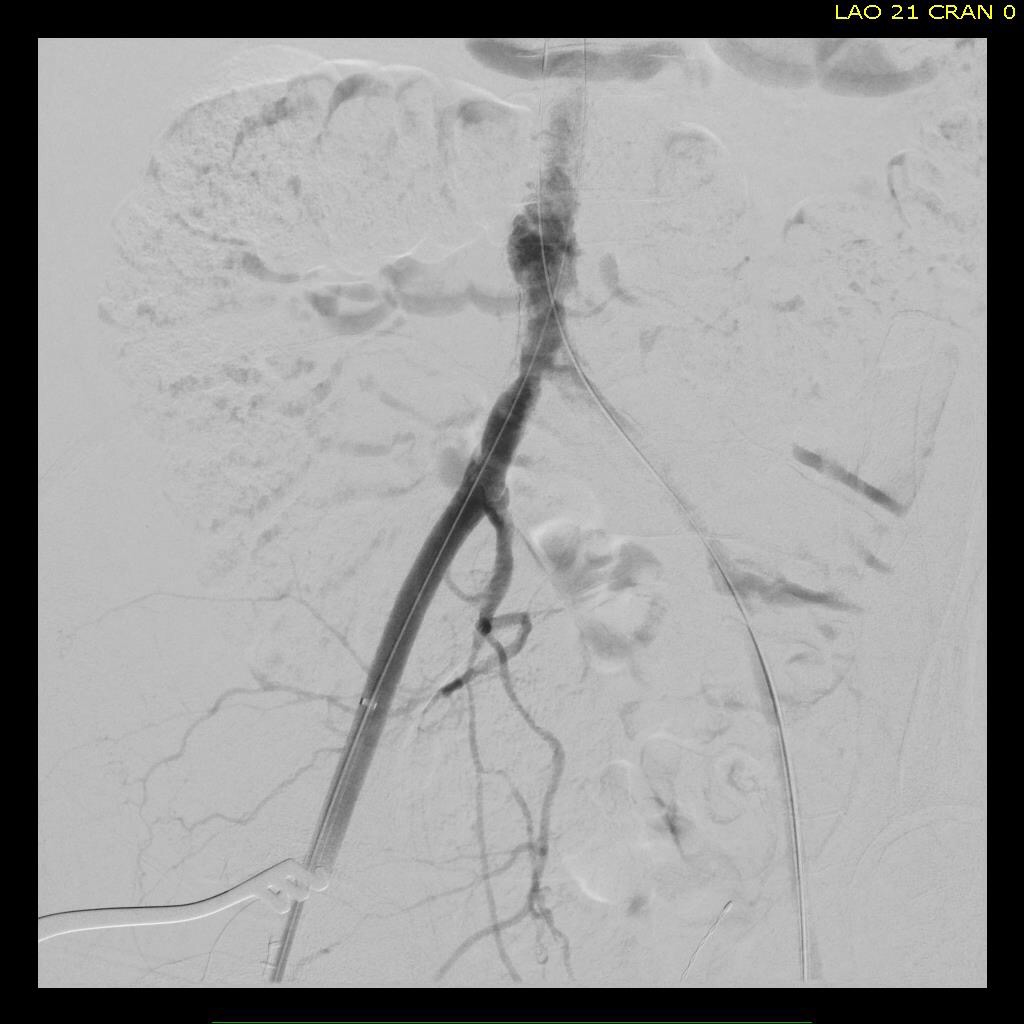

The patient was operated on in a hybrid endovascular OR suite. A right groin incision was made to expose the common femoral artery for endarterectomy and left common femoral access was achieved for angiographic access, but also to place a wire across the occlusion into the common femoral artery.

All actions on the external iliac artery plaque are done with an up-and-over wire, allowing for swift action in the instance that arterial perforation or rupture occur. This event is exceedingly rare when the operation is well planned. With this kind of access, an occlusive balloon or repairing stent graft can be rapidly delivered.

The plaque end point is typically treated with a stent -in this case, the common iliac plaque was also treated.